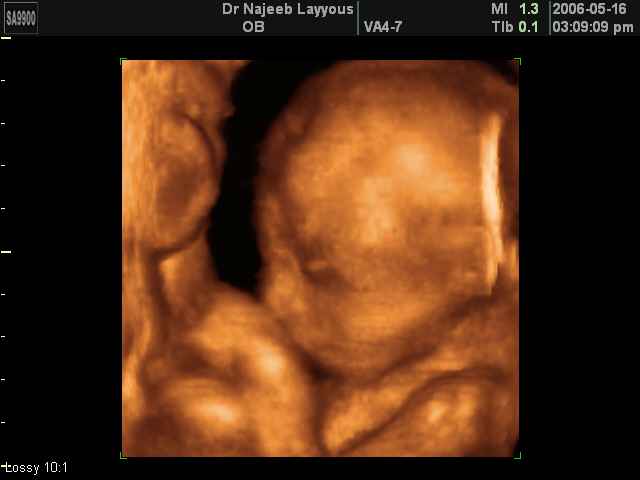

- 3D Fetal Profile Ultrasound Scan Photos

3D Fetal Profile Ultrasound Scan Photos | Dr N Layyous